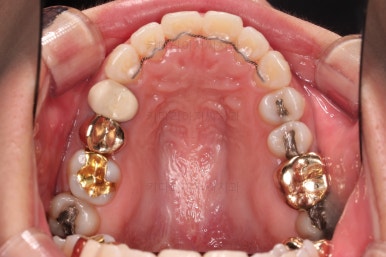

이번에 부산부분치아교정 환자분이 선택하신 장치는 엠파워 클리어라고 하는 자가결찰 세라믹인데요.

흔히들 아시는 클리피씨가 이러한 종류의 장치에요.

아랫니는 일반 브라켓 보다 매우 작은 장치가 들어갔는데요.

미니튜브 장치에요.

일반적으로 MTA 장치라고 많이 알려져 있는데요. MTA라는 상품명과는 다른 장치이긴한데 왜 이 장치를 사용했을까요?

보기도 덜 보이는 장점이 있지만 이번 환자분의 경우에는 아랫니가 약간 솟구쳐 오르면서 장치를 부착하게 되면 씹혀서 매우 불편감이 예상되었었어요.

그래서 초기 정렬단계에서는 미니튜브를 이용해 주고, 추후에 좀 더 정교한 조절이 필요한 상황에서는 브라켓장치(엠파워 클리어)로 재부착하기로 했어요.

그리고 아랫니 송고니 옆 잇몸에 보시면 미니스크류가 식립이 되어있는데요.

이는 솟구친 아래 앞니의 높이를 조절하기 위해 사용이 됩니다.

이부분이 해결이 되어야 좀 더 완성도 높은 부분교정이 가능해요.